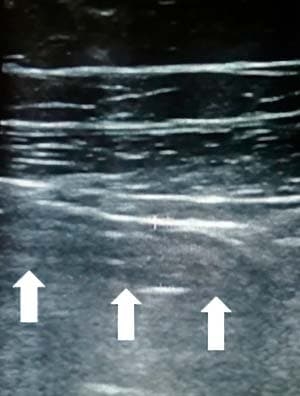

Ультразвуковая картина нормального аппендикса

Неизмененный аппендикс при УЗИ найти удается редко, он определяется как слепо заканчивающаяся, слоистая трубчатая структура, легко сжимаемая при компрессии; диаметр обычно меньше 6 мм. Нормальный аппендикс подвижен, может иметь спавшийся просвет, но также может содержать газ, редко — небольшое количество жидкости (см. рис. 21, 22).

Рисунки 21, 22. Нормальный червеобразный отросток.

Визуализация нормального аппендикса позволяет исключить диагноз острого аппендицита.